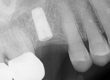

The above sequence illustrates the issue of defining the spot. Retrospectively, the spot could have been more toward 5 o’clock, but under normal circumstances this would have been more than adequate. Starting the .8mm bore is the next step in the sequence.

.8mm slightly inside of the spot and is cropped in the second image. This photograph is centered on the visible outline of the fragment.

.8mm bore is deepened with a slight progressive drift toward 9 o'clock from image 2 to 4. Clinically, this was hard to appreciate at this level of detail with the top 1/2 of the screw outline missing.